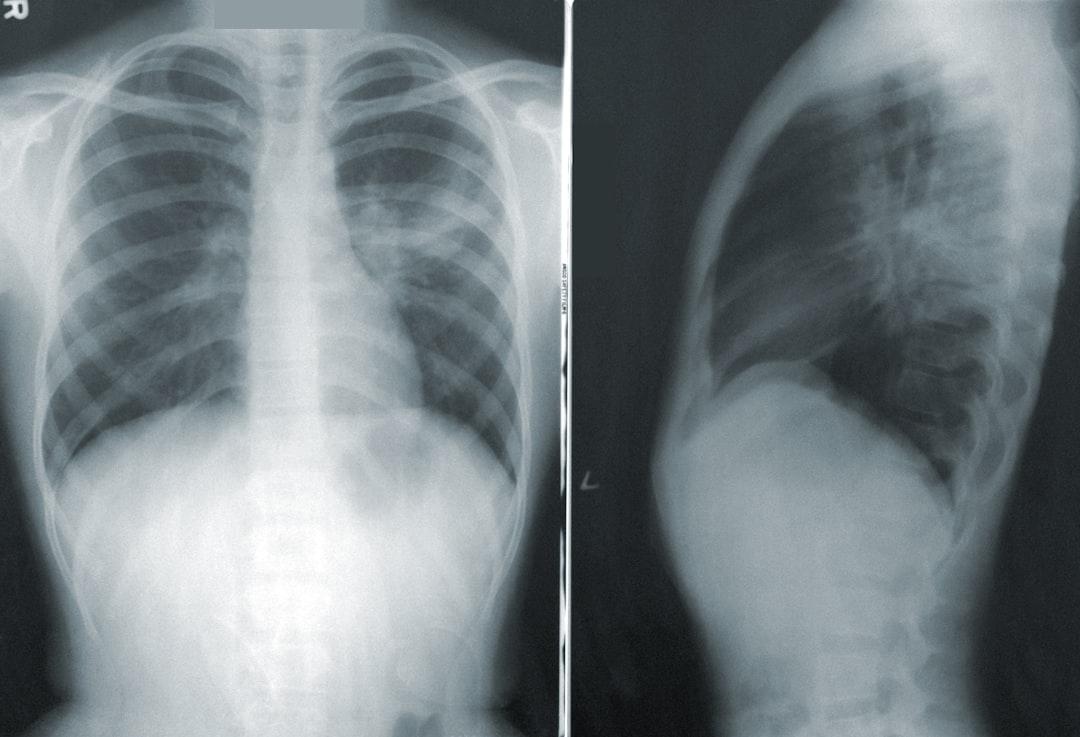

Viêm phổi do phế cầu dễ phát tác trong mùa đông

Phế cầu là nguyên nhân chính gây viêm phổi do vi khuẩn sinh mủ, gây tổn thương ở phổi, nhiễm khuẩn máu và có tỷ lệ tử vong cao, đặc biệt ở người lớn tuổi. Tiêm vaccine là biện pháp phòng ngừa hiệu quả.